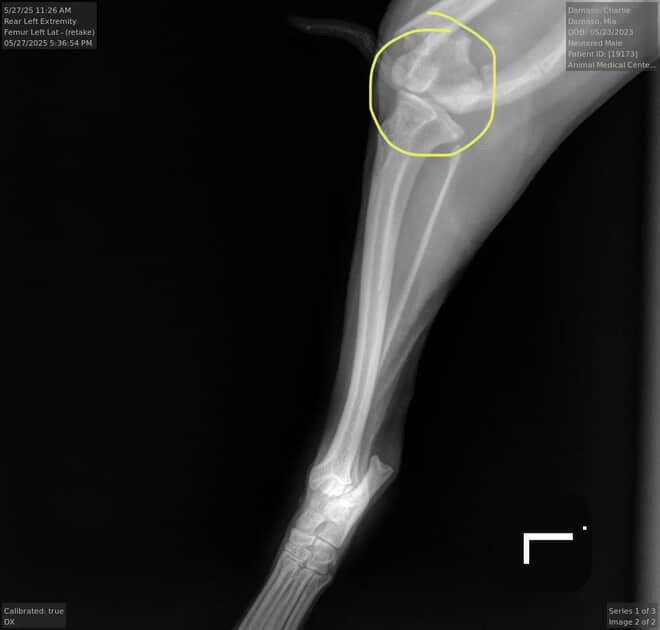

Hello everyone and thanks for taking the time to read this! The reason I’m creating this GoFundMe account is because Charlie, my niece's chihuahua, was accidentally hurt at the hands of my 6 y/o son. His leg ended up being broken and the vet says he needs surgery.